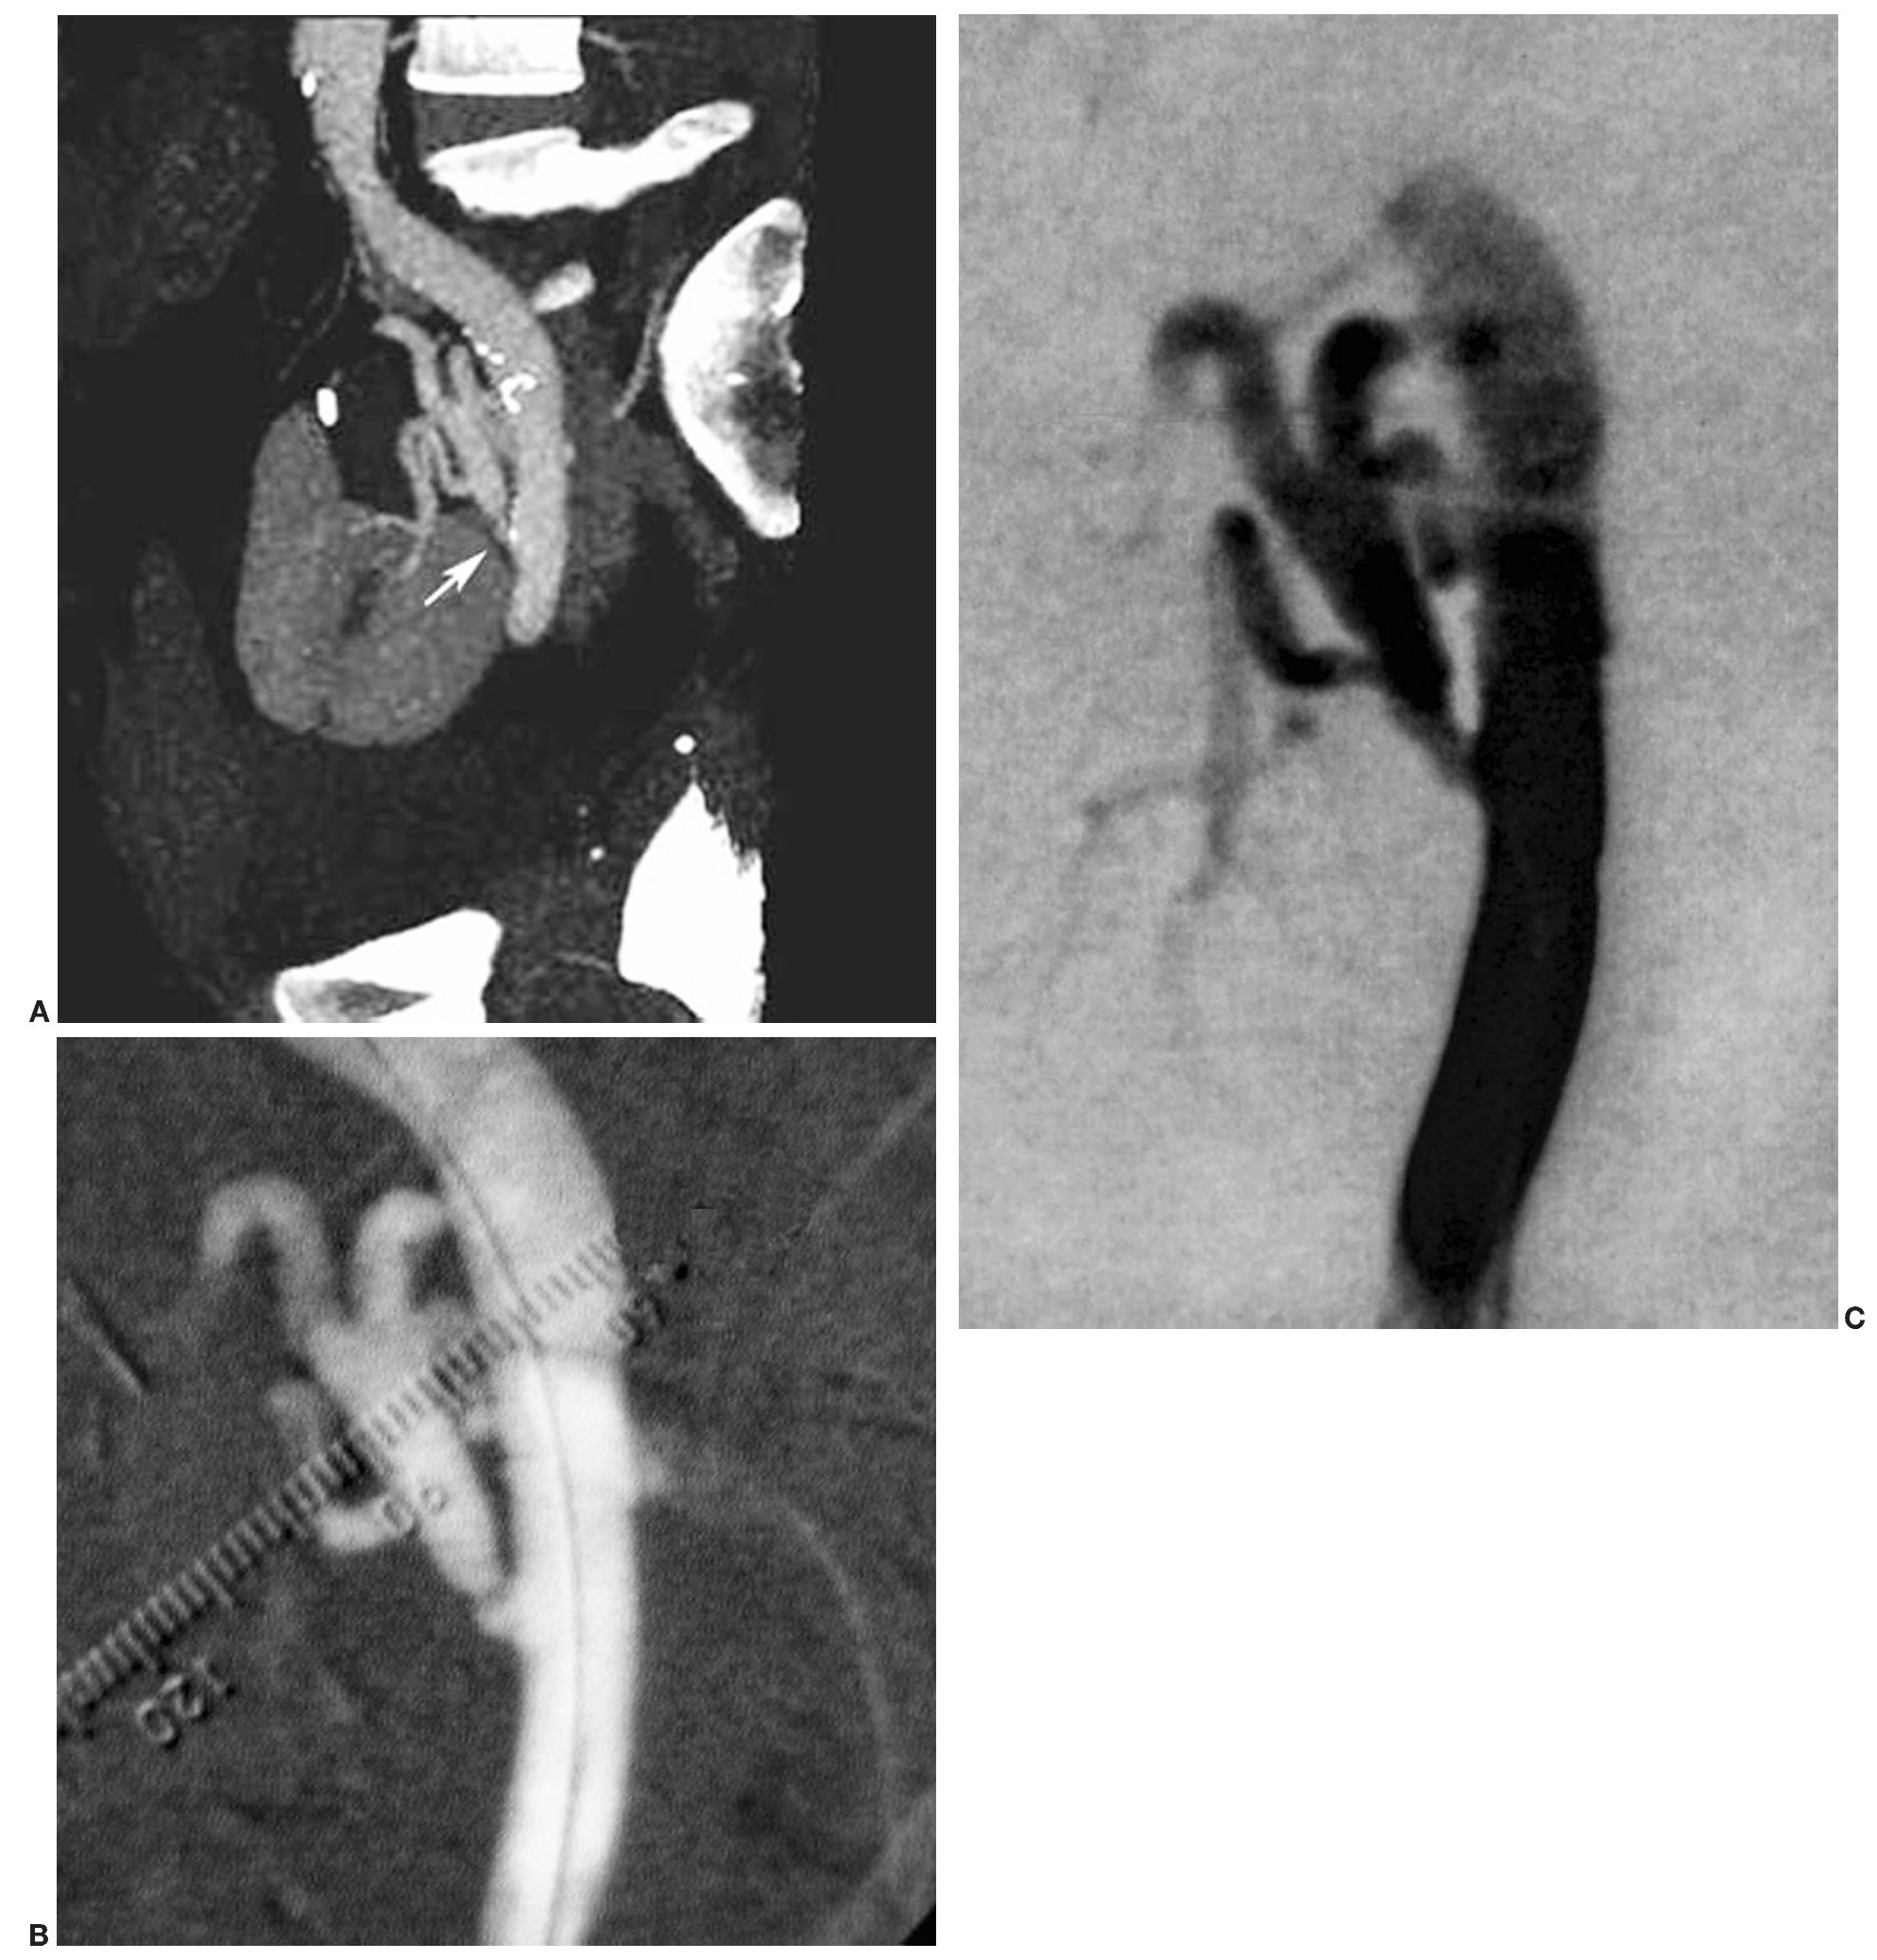

En TCMC se detectaron signos de displasia fibromuscular en tres arterias renales, y fueron clasificadas como estenosis de grado II. Estos hallazgos fueron corroborados tras la realización de la ASD. De los dos pacientes portadores de sendos injertos renales, en uno se diagnosticó correctamente una estenosis de grado III en la anastomosis quirúrgica de la arteria del injerto (fig. 3). En el otro paciente, la arteria del injerto presentaba un aspecto filiforme, en el límite de resolución de la TCMC. Se decidió, por tanto, cotejar su evaluación con la práctica de una ASD en la que se descartó de forma tajante una estenosis significativa potencialmente tratable. También se diagnosticó en la TCMC una disección espontánea de arteria renal, pero sin embargo esta lesión no se confirmó en la ASD (fig. 4). En el resto de casos en los que se detectó patología arterial se consideró la causa ateromatosa como factor etiológico.

Fig. 3. (A) Reconstrucción oblicuo coronal de máxima intensidad de señal centrada en la anastomosis quirúrgica entre la arteria ilíaca y la arteria renal de un injerto renal a nivel pélvico. Estenosis grado III en la arteria del injerto (flecha). (B) Angiografía con sustracción digital (ASD) en la que se demuestra la estenosis preoclusiva en el punto de la anastomosis. (C) En la ASD de control, tras la realización de una APT con balón de 6-20 mm, se aprecia una mínima estenosis residual.

Fig. 4. (A) Reconstrucción coronal de máxima intensidad de señal en la que se identifica una imagen de doble pared en la vertiente inferior de la arteria renal principal izquierda, que sugiere una disección espontánea. (B) En la angiografía con sustracción digital se observa una arteria íntegra y de características normales, descartándose el diagnóstico inicial de disección. El hallazgo muy probablemente fue motivado por un artefacto de vigoroso pulso arterial.